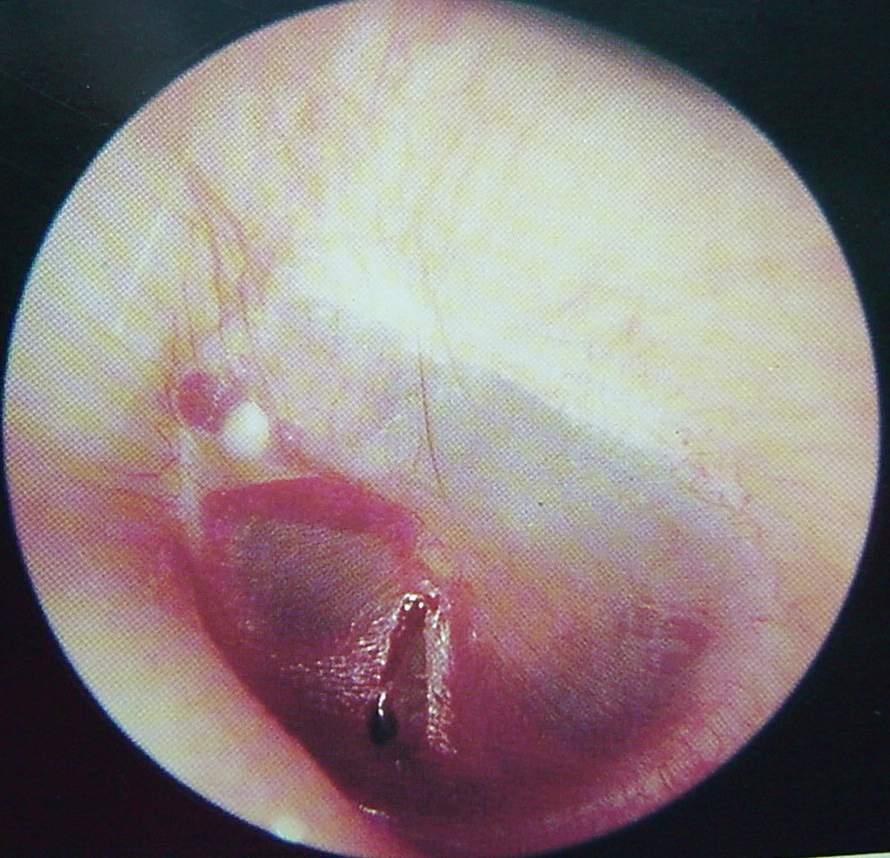

Ear Clinical Photos for Static Stations